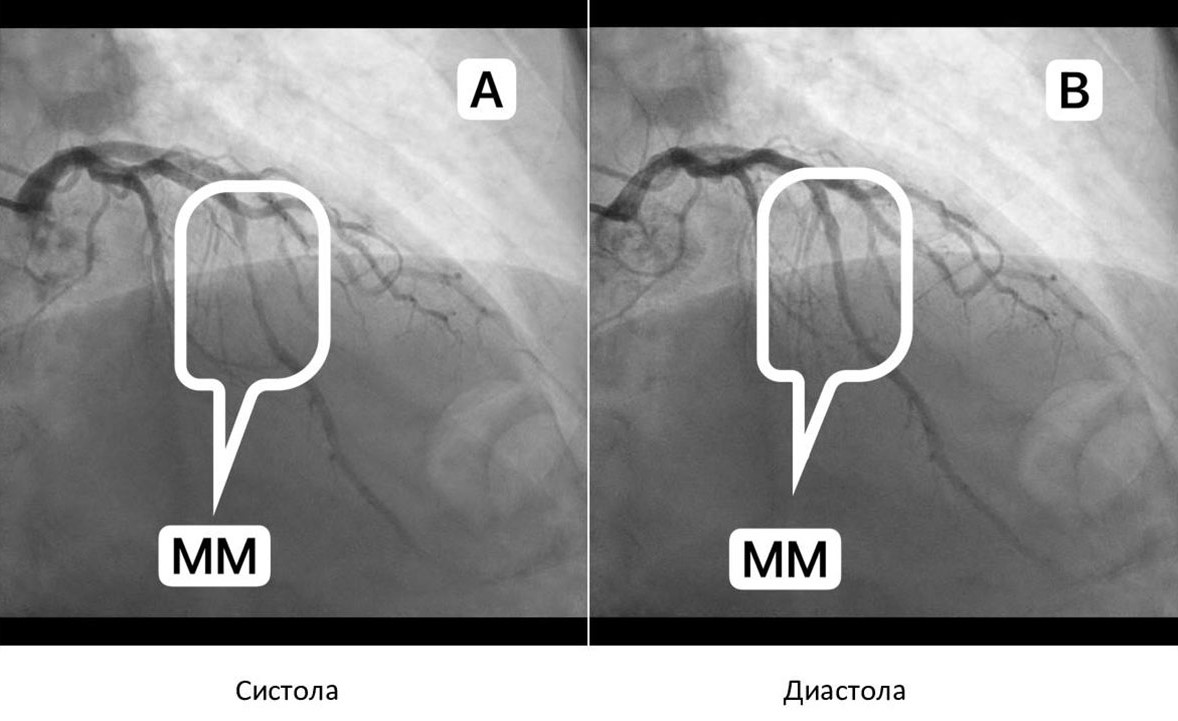

В ряде исследований при многофакторном анализе с учетом возраста пациентов, наличия у них сахарного диабета и кардиомиопатии была достоверно установлена взаимосвязь ПАБ в ПМЖВ, в частности, наличие ММ значительно повышает риск коронарного атеросклероза [3, 4, 8, 11, 16–18]. В проксимальном сегменте коронарной артерии атеросклеротические изменения в стенке сосуда выявляются в 98% случаях, при этом сегмент самого ММ никогда не подвергается атеросклеротическим изменениям, так как в стенке сосуда отсутствуют гладкие мышечные клетки синтетического типа, которым отводится главная роль в формировании атеросклеротической бляшки [19]. Более высокие градиенты давления в артериальных сегментах, расположенных проксимальнее ММ, могут быть наиболее мощной движущей силой для проникновения холестерина в субэндотелиальные слои, если у пациентов высокий уровень холестерина. Попадание холестерина, частиц липопротеинов фагоцитирующих клеток можно определить как «эффект засева» при высоком градиенте давления только в проксимальном сегменте туннелированной артерии (рисунок 3).

Рисунок 3. А. ММ в дистальной трети ПМЖВ (прямоугольник) с проксимальными атеросклеротическими бляшками (стрелки). В. ММ в средней трети ПМЖВ (прямоугольник) с проксимальными атеросклеротическими бляшками (стрелки).

Figure 3. A. The myocardial bridge in the distal third of the LAD (rectangle) with proximal atherosclerotic plaques (arrows). B. Myocardial bridge in the middle third of the LAD (rectangle) with proximal atherosclerotic plaques (arrows).